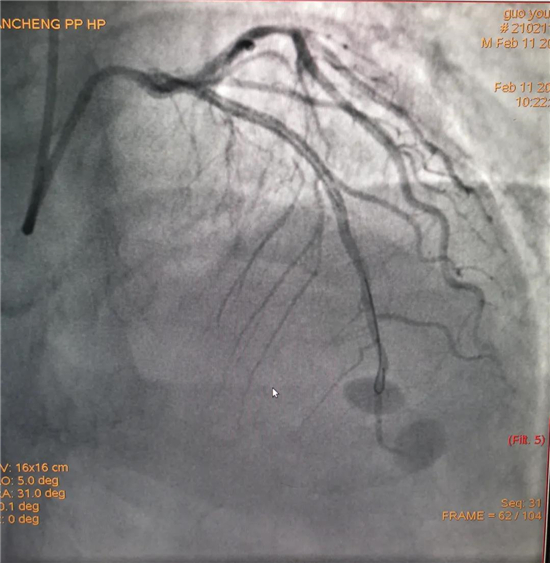

除夕,郭先生無(wú)明顯誘因突發(fā)胸痛,120急救人員到達(dá)現(xiàn)場(chǎng),心電圖顯示:竇性心律完全性束支傳導(dǎo)阻滯。信息立刻發(fā)送到胸痛中心介入微信群中,心內(nèi)科值班醫(yī)生初步診斷為急性廣泛前壁心肌梗死,必須盡快進(jìn)行急診支架治療,開通血管。值班醫(yī)生電話指導(dǎo)院前治療,并立即啟動(dòng)胸痛綠色通道,24小時(shí)備班的介入治療團(tuán)隊(duì)立即到位,9:30患者被送到導(dǎo)管室行冠脈介入診療,9:40急診PCI手術(shù)隨之開始,冠脈造影檢查提示左前降支閉塞,植入支架,堵塞的血管被順利打通,患者癥狀緩解,手術(shù)非常成功,10:20患者被送往病房進(jìn)一步治療。